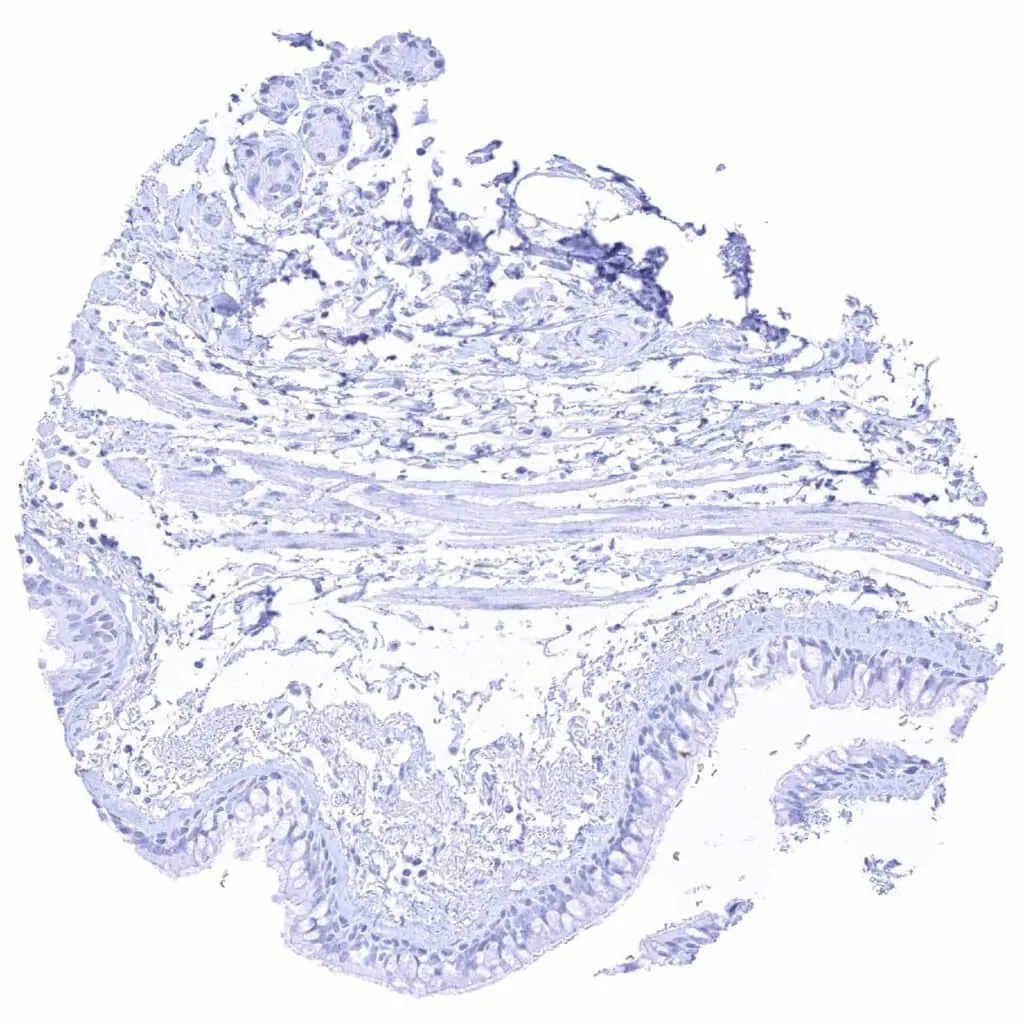

Placenta, mature, amnion and chorion

Placenta, mature